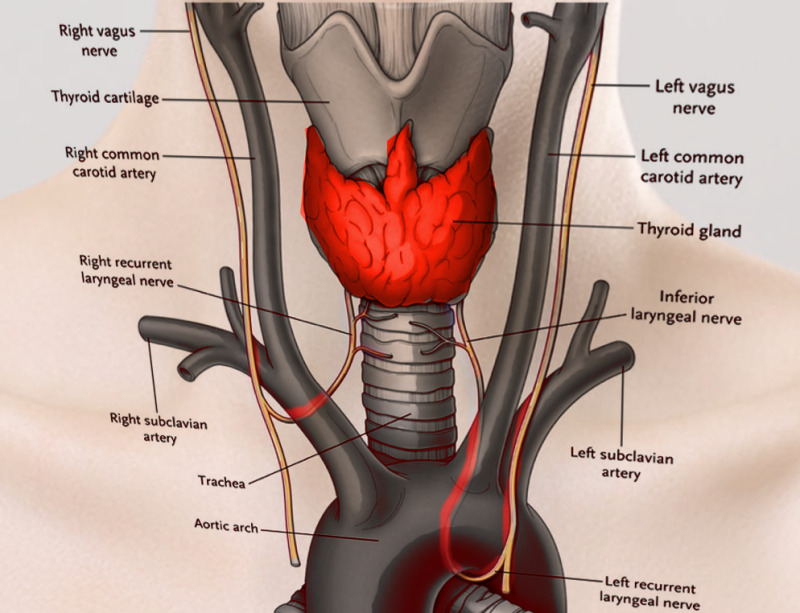

Vagus n. (CN X)

Name the nerve

Superior laryngeal n.

Name #3

Internal branch of superior laryngeal n.

Inferior laryngeal n.

Name the left recurrent laryngeal n.

Left recurrent laryngeal n.

Name the right recurrent laryngeal n.

Right recurrent laryngeal n.

Know the common carotid a.

Common carotid a.

Know the internal carotid a.

Internal carotid a.

Know the external carotid a.

External carotid a.